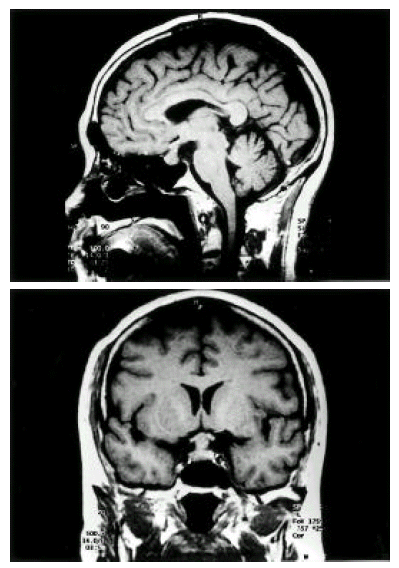

Figure 2.

Pituitary fossa MRI show isodense signal intensity mass occupying the pituitary fossa and infundibular thickening.

A 69-year-old female housewife complained of a sudden onset of dry mouth, polyuria and polydypsia two months prior to admission. She had been in good health and had no particular medical history. Two months ago, she developed abdominal pain, loose stool, general weakness, malaise, nausea, dry mouth and polyuria. On admission, neurologic examination was done but no particular pathologic findings, including visual field defect, were observed. On admission, she showed chronic ill-looking appearance, a dehydrated tongue and dry skin. Urine volume was 3500–4500 mL a day and urinalysis showed a specific gravity of 1.005, urine osmolarity 227 mOsm/kgH2O, Na 101 mmol/L, K 10 mmol/L and Cl 84 mmol/L. Plasma osmolarity showed 294 mOsm/kgH2O, Na 146 mmol/L, K 3.3 mmol/L and Cl 111 mmol/L. We performed an endocrinological study. The study demonstrated partial hypopituitarism (serum cortisol 1.33 μg/dL, ACTH 16.86 pg/mL, total T3 58.8 ng/mL, total T4 4.8 μg/dL, TSH 0.24 mlU/mL, LH 1.38 mlU/mL, FSH 0.24 mlU/mL, ADH 1.28 ng/mL). Anterior pituitary function was investigated with a set of three tests with insulin tolerance, TRH and LHRH. Cortisol, TSH, FSH and LH responses were compromised, while prolactin responses were retained (Table 1). Plain skull X-ray film of the sella was normal (Figure 1). Magnetic resonance image (MRI) scan showed isodense signal intensity mass lesion in pituitary fossa with infundibular thickening and no enhancement of RCC with dynamic study was observed (Figure 2). As the patient presented polyuria, mild headache and hypoosmolar urine, a water deprivation test was done, revealing a pattern of partial central diabetes insipidus (Table 2). In order to obtain an exact diagnosis, surgery was performed via the transsphenoidal approach. Yellow-colored discharge flowed from the cystic lesion when the anterior pituitary was incised. Cyst drainage and wall biopsy were done. The histopathological examination showed mixed inflammatory cell infiltration in the loose connective tive tissue stroma. Leukocyte common antigen (LCA)-positive lymphocytes were detected. Focally remained columnar epithelial walls were noted and cytokeratin immunohistochemical staining revealed monolayered columnar epithelium in the cyst wall (Figure 3, 4). These findings were compatible with Rathke’s cleft cyst inflammation. After operation, the patient was given a physiologic dose of prednisolone, thyroid hormone and desmopressin nasal spray. Polyuric symptoms disappeared with this regimen. Five months later, desmopressin replacement was stopped and no more polyuric symptoms have developed.

RCC arises from the remnants of Rathke’s pouch, an invagination of the stomodeum formed by the fourth gestational week2, 3, 7). Normally, Rathke’s pouch is closed off by proliferation of the anterior and posterior lobe of the pituitary gland, and this lumen forms a thin residual cleft in the gland. The resulting cleft persists as a cyst lined with columnar or cuboidal epithelium of ectodermal origin. Failure of obliteration of Rathke’s cleft with proliferation of the lining cells and accumulation of secretions may result in cyst formation between anterior and middle lobes2, 3). Voelker et al. reviewed 155 cases of RCC saying that RCC is usually asymptomatic and found in 13–22% of normal pituitary glands in autopsy8). RCC is an intrasellar cyst containing mucoid material. RCC shows few symptoms with the size of less than 1 cm. However, when it grows more than 1 cm2–5, 9) or inflammatory changes develop, various symptoms may occur, especially when it expands to the infundibular portion and suprasellar region2–5, 9, 10). Most common presenting symptoms are headache, visual disturbance, hypopituitarism and hypothalamic dysfunction. However, a few cases reported decreased libido, impotence and diabetes insipidus2, 10). Mechanical compression of the pituitary gland by the cyst, as well as inflammation itself, may play a major role in causing pituitary dysfunction in RCC patients9). Lymphoplasmatic inflammation induced by mucus secreted by goblet cells of the cyst wall leads to inflammatory changes of RCC and leakage of cyst contents into the pituitary gland can occur, possibly leading to the development of abscess formation9, 11, 12). Voelker et al. and Ross et al. reported hypopituitarism in 39% and 12% of patients, respectively6, 8). But some authors reported 100% incidence of hypopituitarism9). Thus, subclinical RCC presenting no specific symptom may occur frequently. Eguchi et al. said that RCC greater than 1 cm which develops symptomatic hypopituitarism involving more than two hormones should be treated with a surgical approach as the general recommendation9). The most frequent cases involve hyperprolactinemia, followed by gonadotropin deficiency, pan-hypopituitarism, hypothyroidism and hypocortisolism2). Our case exhibited hypopituitarism without prolactin deficiency. Its size was more than 1.5 cm. It showed isodense intensity on T1-weighted image on MRI. Usually RCC shows hypodense. intensity on T1-weighted image but inflammatory change could be shown as isodense or hyperdense intensity like our case4). Incision of the cyst was made, yellowish pus-like aspirates flowed from the cyst. Accordingly, RCC inflammation and abscess formation were suspected. Biopsy findings revealed mixed inflammatory cell infiltration in the loose connective tissue stroma and focally remained cyst wall composed of columnar epithelium. Cytokeratin immunohistochemical staining revealed monolayered columnar epithelium in the cyst wall. RCC presenting with diabetes insipidus is rare2, 3, 9). Diabetes insipidus is thought to be a result from stalk impairment4). El-Mahdy et al. reports 28 cases of symptomatic RCC treated by transsphenoidal operation and only one of those cases (3.6%) presents diabetes insipidus, while 4 patients (14.3%) suffered preoperatively from diabetes insipidus2). It is important to differentiate RCC from other neoplastic lesions, such as craniopharyngioma and pituitary adenoma1, 3, 4, 13). Differentiation from pituitary adenoma is important as it is very difficult to distinguish RCC from pituitary adenoma3). Preoperative diagnosis in most reported cases were pituitary adenoma. The widening of sella turcica was the common point of differentiation in many cases of pituitary adenoma in simple skull image3). Yoshida et al. reported that the mean age of the patients was 38 years old, and the highest frequency was in the fifth decade with marked female preponderance7). Endocrinological presentation of RCC, such as amenorrhea, is thought to be the major cause of marked female preponderance2, 9). With the advent of MRI, asymptomatic or subclinical RCCs are now being detected with increasing regularity. Simple drainage and partial excision of the cyst wall is the treatment of choice1–5, 9). Wide removal of the cyst wall should be avoided because of possible damage to the hypothalamus, pituitary, optic nerves and optic chiasm1). Transsphenoidal surgery is preferred because there is danger of damage to the hypothalamus and optic apparatus1–5, 9). Surgical treatment is generally recommended even when the patient has mild symptoms or signs such as headache, mild defect of visual field, increased prolactin or a cyst size of more than 10 mm9). Patients with small-sized RCC, or even asymptomatic, should be followed up regularly with an MRI. Systematic endoclinological examination is recommended once a year9). Generally, the prognosis after a partial removal of the cyst wall or simple aspiration of the cyst seems to be good even though the cyst recurs2, 3).